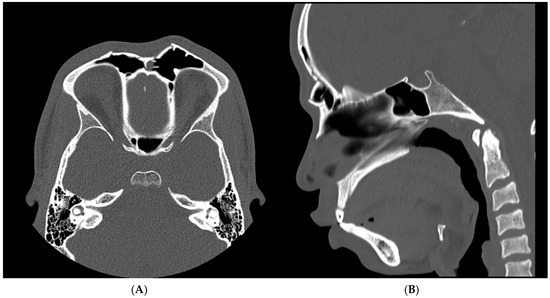

Background/Objectives: Frontal sinus fractures are uncommon injuries that may cause persistent aesthetic deformity when the anterior wall is comminuted, as small irregular fragments are difficult to stabilize with conventional osteosynthesis alone. Methods: We describe a point-of-care digital workflow combining 3D planning/printing and cyanoacrylate-assisted [...] Read more.

Background/Objectives: Frontal sinus fractures are uncommon injuries that may cause persistent aesthetic deformity when the anterior wall is comminuted, as small irregular fragments are difficult to stabilize with conventional osteosynthesis alone. Methods: We describe a point-of-care digital workflow combining 3D planning/printing and cyanoacrylate-assisted fixation for an isolated comminuted anterior frontal sinus wall fracture. A young adult presented with a depressed forehead contour after assault; computed tomography confirmed at least four displaced fragments. Results: A two-part 3D-printed biomodel was manufactured in-house to visualize the defect and guide extracorporeal reconstruction. Through a coronal approach, fragments were mobilized and anatomically reassembled using the biomodel as a reference; sinonasal drainage was preserved and sinus obliteration was not required. Because fragment size and geometry limited screw purchase, a modified N-butyl-2-cyanoacrylate adhesive (Glubran 2) was applied as an adjunct to maintain reduction, followed by reinforcement with titanium microplates. Postoperative recovery was uneventful, with immediate restoration of forehead contour and no early complications; postoperative imaging confirmed satisfactory alignment. Conclusions: This case supports the feasibility of integrating point-of-care 3D biomodeling with cyanoacrylate as a coadjuvant to microplate fixation in selected comminuted frontal sinus fractures to enhance fragment handling and contour restoration. Full article